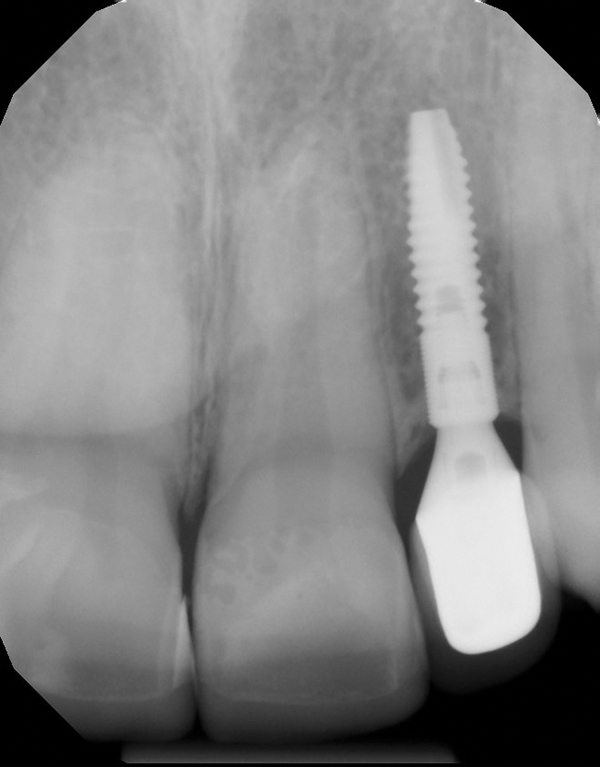

Fig 9 and Fig 10. An implant placed in site No. 10.

When the patient was 18 years old, an implant was placed in site No. 10 with no complications (Figure 9 and Figure 10). Three months later, a periapical radiograph was taken, the implant was torque tested, and a healing abutment (3 mm by 4 mm by 4 mm) was placed.